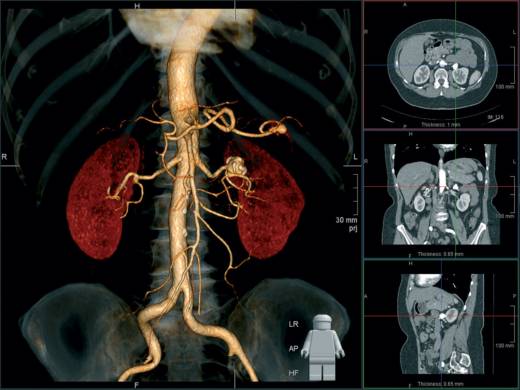

Томографические исследования

Компьютерная и магнитно-резонансная томография — самые современные методы диагностики пиелонефрита. С их помощью можно наиболее точно изучить анатомические особенности не только самих почек, но также их сосудистой системы и окружающих органов. С помощью этих методов диагностируются камни, аномалии строения, особенности кровотока и определяется способность почек фильтровать кровь. В двух последних случаях в вену пациента вводится контрастный препарат, как при проведении экскреторной урографии. Однако результат при использовании томографии значительно более подробен.

Томография — исключительно информативное исследование анатомии почек

Метод получения изображения при компьютерном и магнитно-резонансном обследовании существенно различается. В первом случае используется рентгеновское излучение, во втором — магнитное поле. Главным недостатком компьютерной томографии является лучевая нагрузка. Магнитно-резонансное исследование запрещено при наличии имплантированных в организм металлических конструкций — кардиостимуляторов, штифтов, болтов и т. д. Однако это исследование не оказывает патологического влияния на развивающийся плод при беременности.

Эффект ядерно-магнитного резонанса используется для подробного изучения анатомии почек